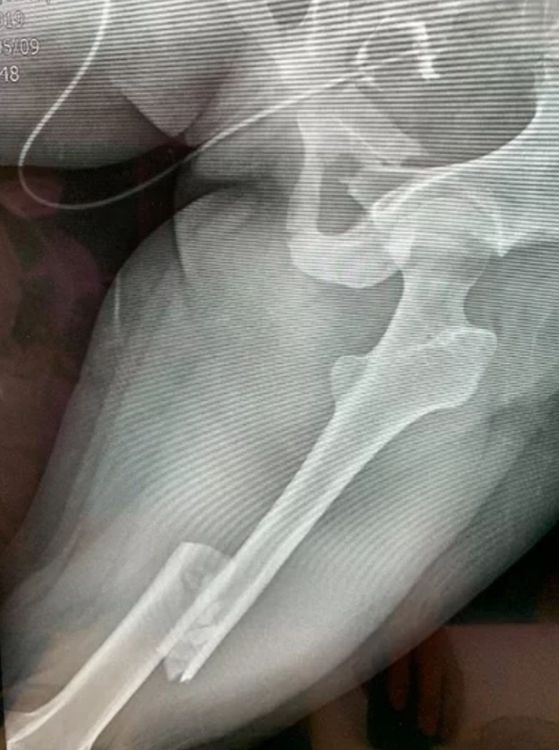

從X光片下發現,吳女骨盆嚴重骨折,會陰部撕裂傷。民眾提供

這場事故吳女雖撿回一命,但她下半身嚴重受傷,包含骨盆骨折、左側大腿骨骨折、第五腰椎骨折、右側肩胛骨骨折、四肢多處擦挫傷。醫生事後表示,患者康復時間恐怕要長達半年,日後還得持續復健,才有機會恢復原來健康身體。